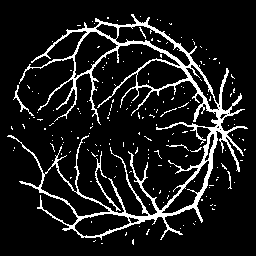

Vessel Extraction

Experiments are implemented on the Digital Retinal Images for Vessel Extraction database (DRIVE) proposed for studies on the extraction of blood vessels (Staal et al. 2004). Models are trained after reshaping all data at 256256 size. Rand score and information theoretic score is also used as evaluation metrics.